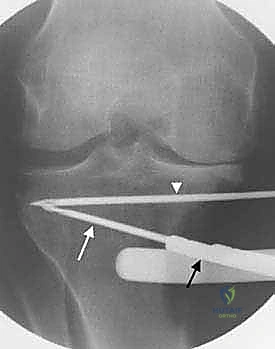

3. إجراء القطع العظمي (The Osteotomy):

باستخدام أدوات دقيقة ومناشير جراحية متطورة، يتم عمل قطع غير مكتمل في عظمة الساق. هناك طريقتان رئيسيتان:

* الشق المفتوح (Opening Wedge): يتم فتح العظم من الداخل وإضافة طعم عظمي (صناعي أو طبيعي) لملء الفراغ وتعديل الزاوية. وهي الطريقة الأكثر شيوعاً حالياً.

* الشق المغلق (Closing Wedge): يتم إزالة إسفين (مثلث) صغير من العظم من الجهة الخارجية وإغلاق الفراغ.

4. تعديل المحور:

يتم فتح العظم تدريجياً وببطء شديد حتى الوصول إلى الزاوية التي تم حسابها في التخطيط الرقمي قبل الجراحة.